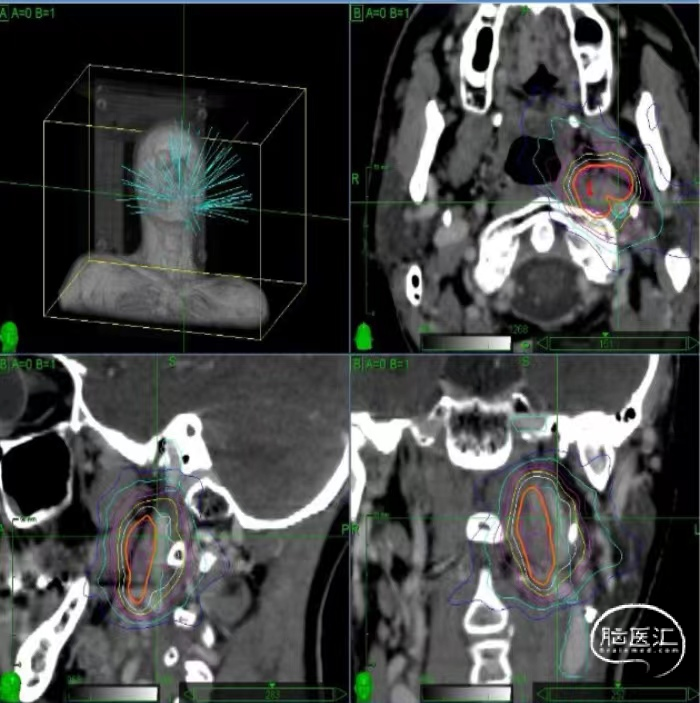

放射性治疗是目前头颈部原发及转移肿瘤的重要治疗方案。然而,放疗在发挥抗肿瘤疗效的同时,不可避免地会损伤放射野内神经、血管及大脑实质等健康组织,导致放射性脑损伤,并产生一系列中枢神经系统损害症状,包括认知功能损害等。

放射性脑损伤所致认知功能障碍是一种排他性诊断,排除原发肿瘤及并发症所致大脑损害以及其他常见的痴呆病因(如:阿尔兹海默病、血管性痴呆等),结合头颈部肿瘤相关放疗史,影像学检查有放射性脑损伤病灶,神经认知心理量表评估(MMSE、MoCA认知评估量表等)有客观认知功能损害证据,可考虑为放射性脑损伤所致认知功能下降。